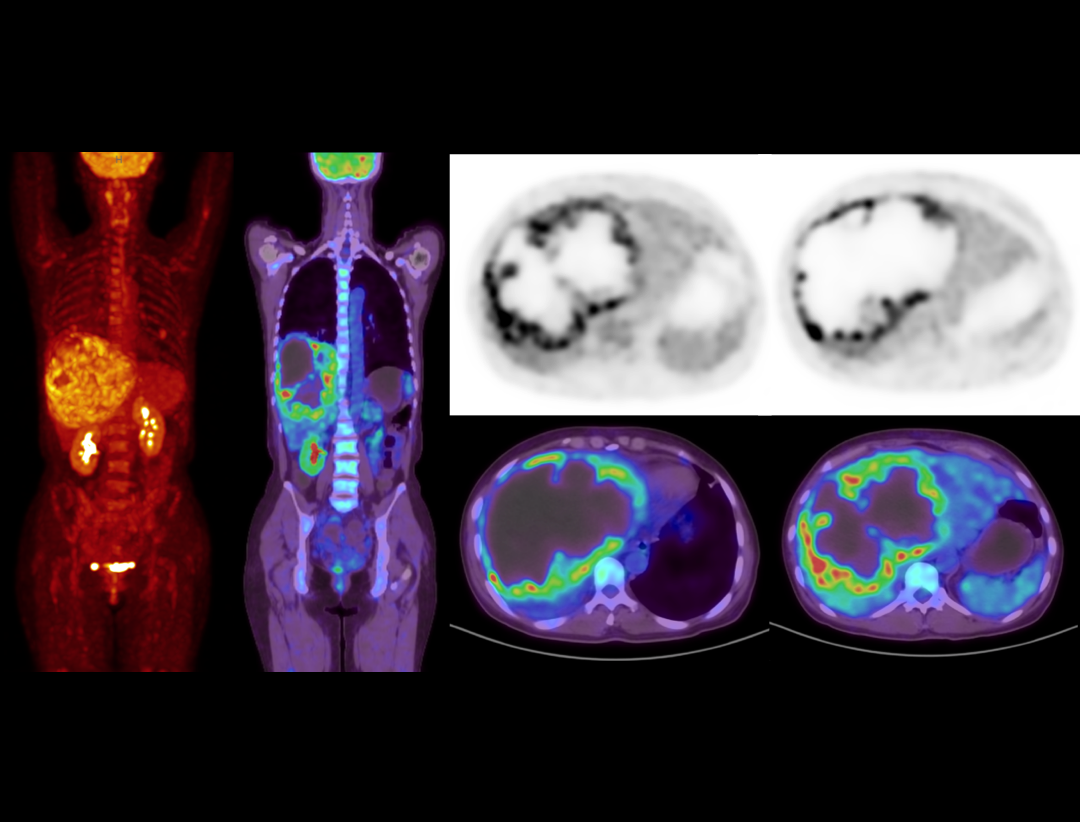

With the unique Integrated-Light-Guide Digital PET technology and a 160-slice CT system, uMI Vista combines high quality functional images with fine anatomical structure visualization. The state-of-the-art reconstruction technology and comprehensive applications further boost diagnostic precision in oncology, neurology and cardiology.

Clarity Imaging Chain

2.9mm NEMA Resolution

Outstanding resolution performance is achieved through systematic imaging chain engineering.

HYPER Iterative Reconstruction

Improves signal-to-noise ratio and contrast recovery to aid lesion detectability and quantitative accuracy.